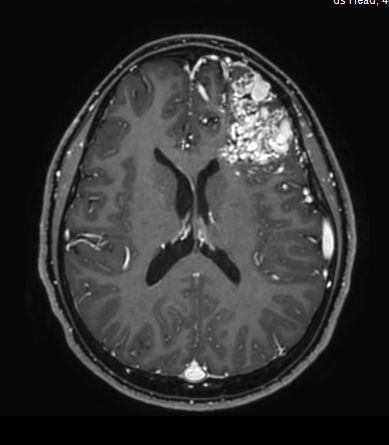

3D T1w TFE +gado - Axial reformatCompressed SENSE

-